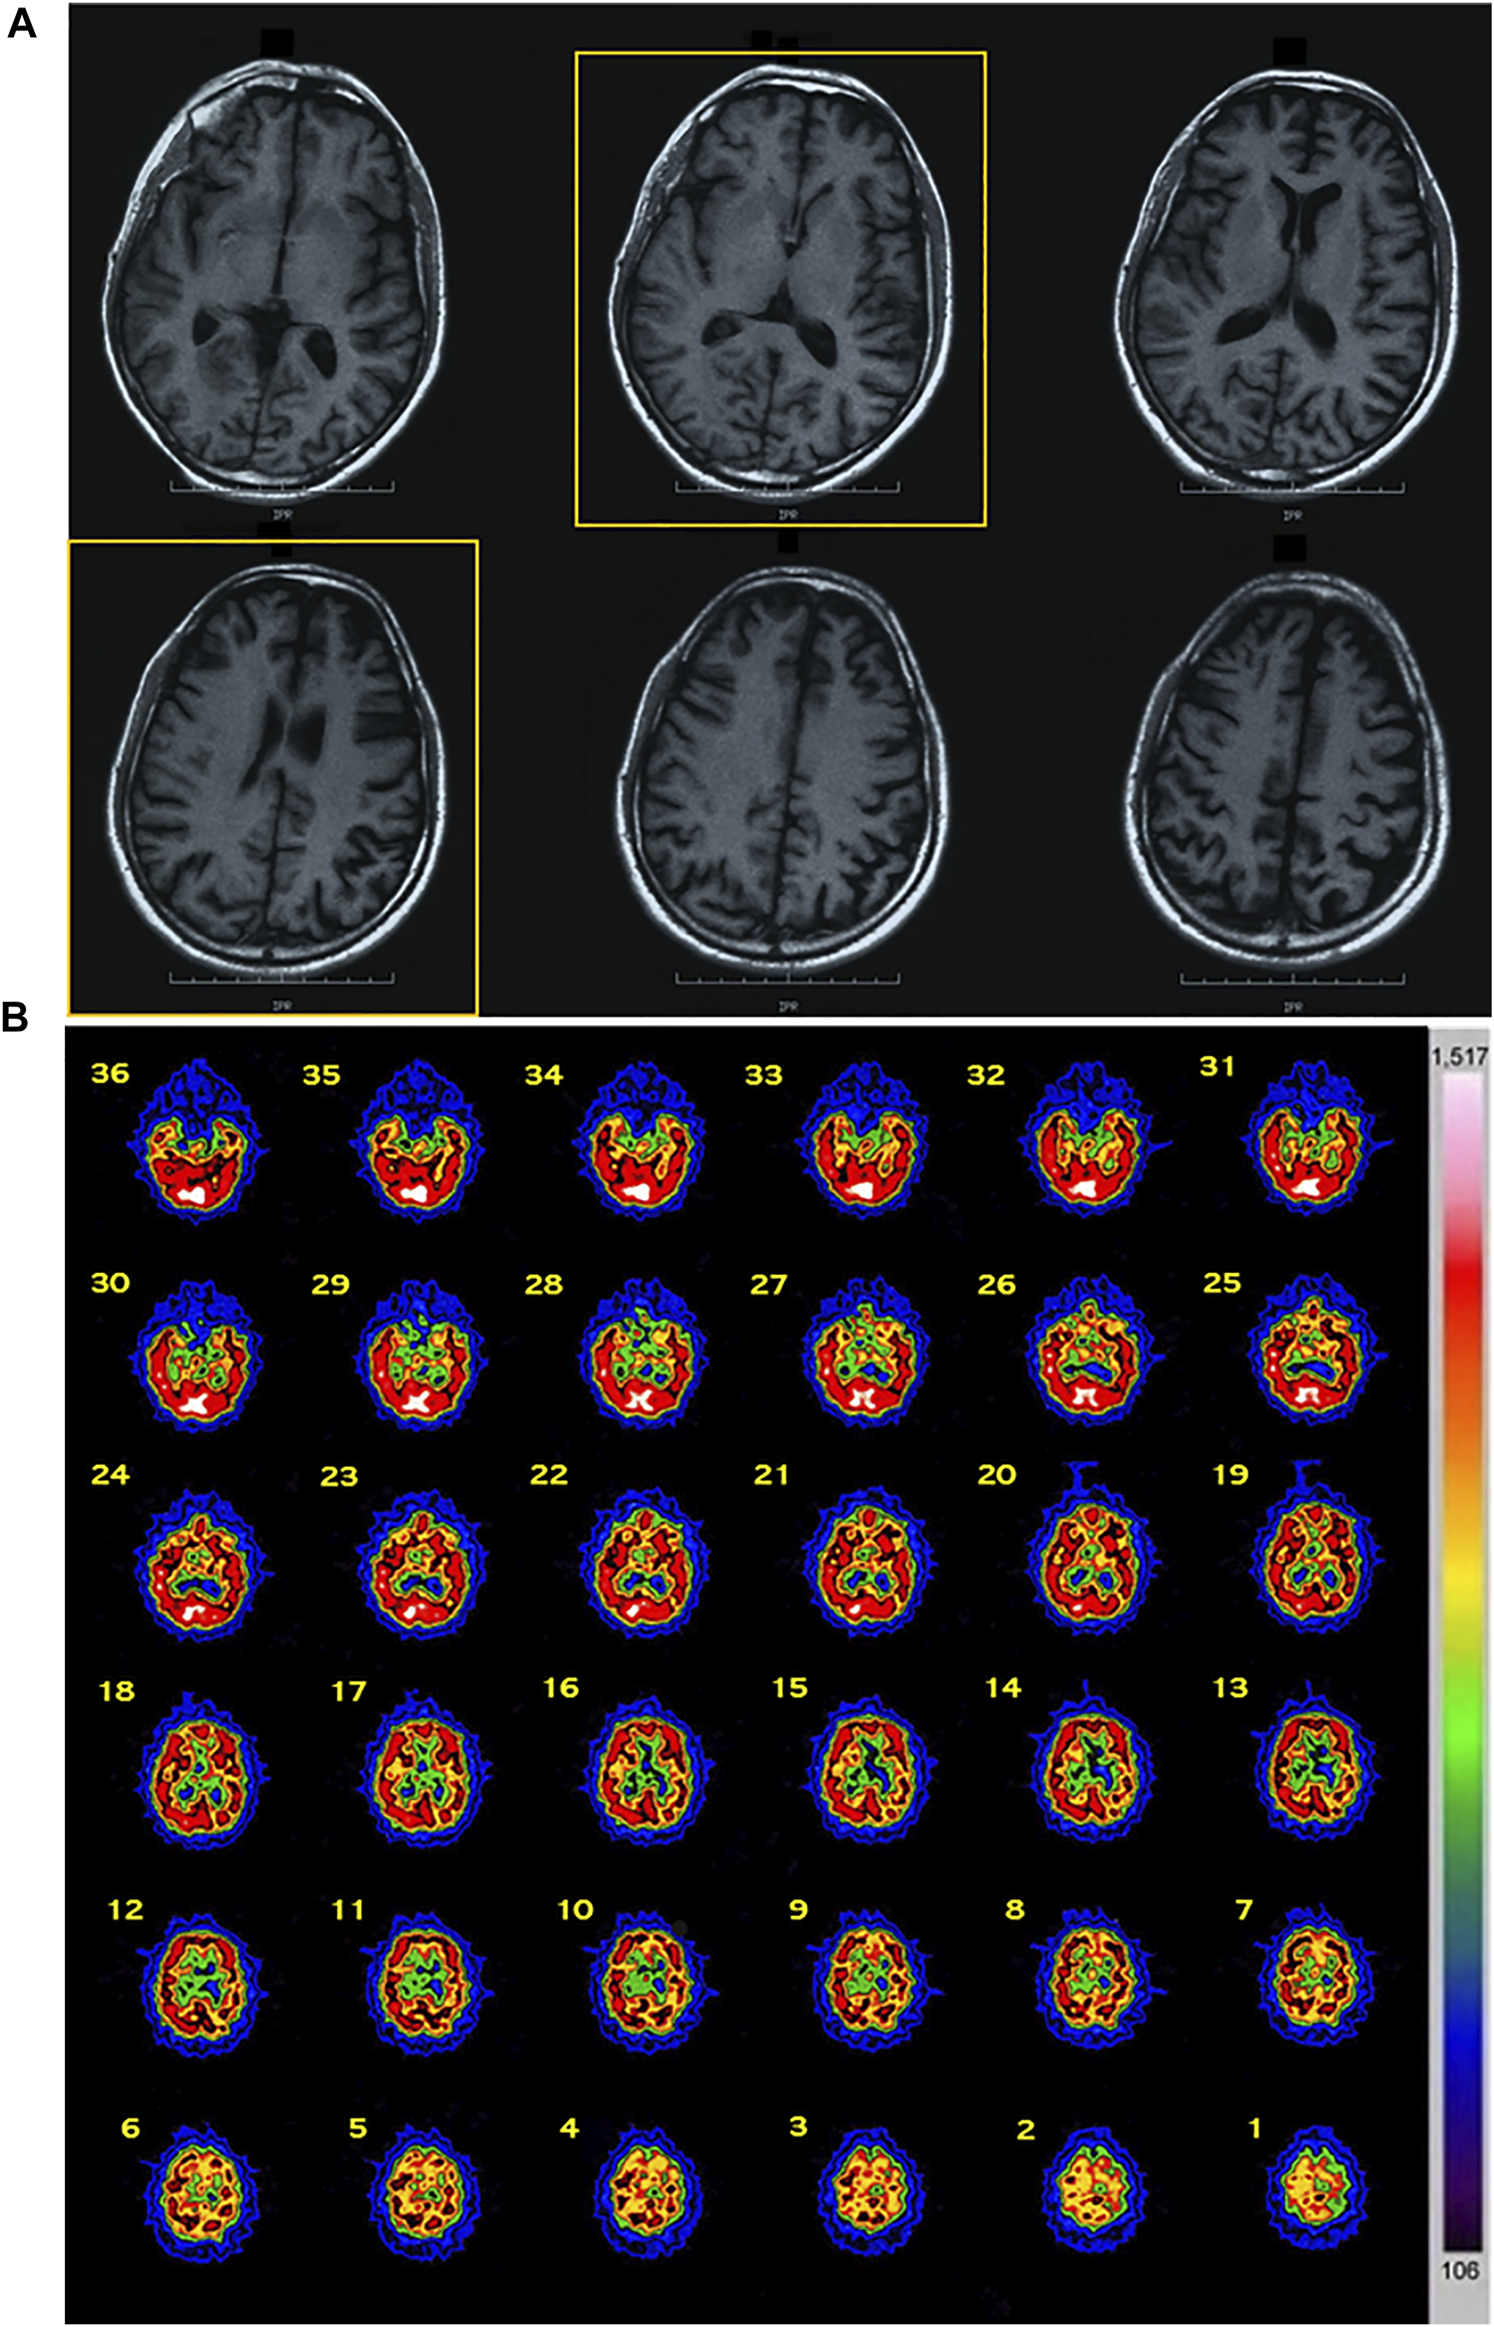

Patient 1 (II-3): The proband was a 40-year-old male. From the age of 35 years, the patient developed progressive behavior abnormalities including apathy, social withdrawal, emotional blunting delusions, agitation, and aggression. During the following months, he presented progressive inattention and memory impairment with loss of personal hygiene habits. EEG, performed at the age of 38 years, manifested an angular aspect delta lens waves diffused with left frontotemporal prevalence. At 40 years old, he was evaluated at our center because of progressive deterioration of criticism and judgment, abilities, stereotypies, and ritualistic behaviors (he picked up cigarette butts on the streets and tried to smoke them), and he presented lack of disease insight. Neurological examination revealed ideomotor apraxia and rooting reflex. Neuropsychological evaluation showed a widespread severe impairment of cognitive functions with predominant involvement of frontal lobe functions. His score on MMSE was 14.9/30 and 2 on the CDR scale. Afterward, about 3 years after his first observation, bulimia (eats uncooked foods), visual hallucinations, hetero-aggressiveness (Neuropsychiatric Inventory, NPI = 68), hyperorality, hypersexuality, manifestations of self-harm, and almost absent language appeared together with generalized epileptic seizures. At 46 years old, in the end stage of his disease, cognitive deterioration was severe with prominent executive dysfunction and marked behavioral disturbances, and finally he showed a severe frontal dementia. He became uncommunicative, rigid, incontinent, and loss of ability to perform activities of daily living (Activities of Day Living, ADL = 2; Instrumental Activities of Daily Living, IADL = 1). He died at 47 years because of intercurrent infections. Routine blood examinations including serum creatine phosphokinase (CPK) and alkaline phosphatase (AP) revealed no abnormalities. Brain MRI showed diffuse cortical atrophy prominent in frontal and temporal regions (Figure 1A). Brain SPECT confirmed these findings revealing a hypoperfusion in frontal and temporal convolutions of the left hemisphere and upper frontal circumvolution of the right hemisphere (Figure 1B).

FIGURE 1

Imaging data of the proband. (A) MRI data: diffuse cortical atrophy prominent in frontal and temporal regions was present. (B) SPECT data: a hypoperfusion was observed in frontal and temporal convolutions of the left hemisphere and upper frontal circumvolution of the right hemisphere. Abbreviations: MRI, magnetic resonance imaging; SPECT, single-photon emission computed tomography.